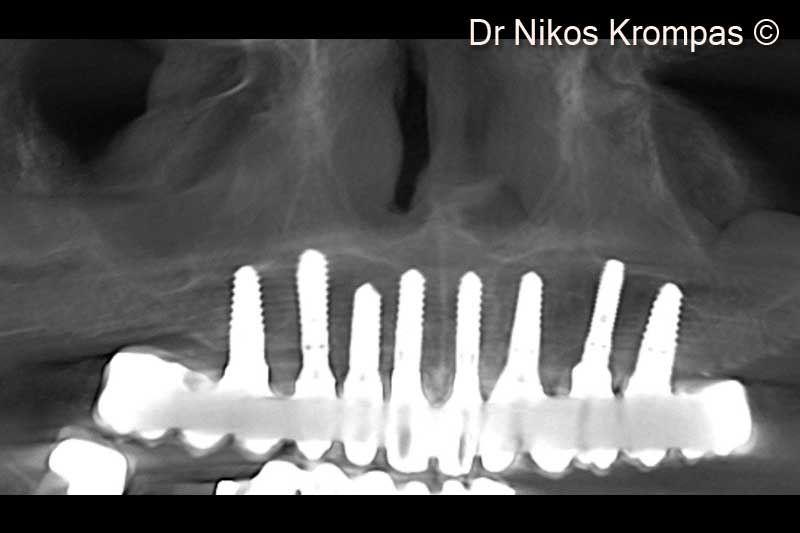

9. Radiograpic view of implants and provisional immediate load bridge